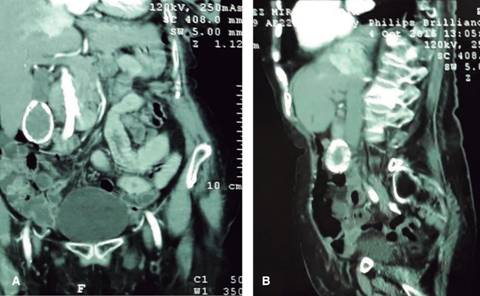

Figura 3: Tomografía computarizada de abdomen con doble contraste, (A) corte coronal; (B) corte sagital, mostrando: hiperdensidad en anillo, en el trayecto de la pared vesicular “en porcelana” a nivel del nacimiento de las arterias iliacas.